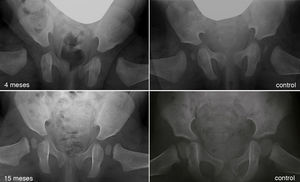

Al avanzar la edad del niño se hace menos probable que la reducción consiga por si sola normalizar el acetábulo displásico29. La prevalencia de «displasia residual» incrementa con la edad a la que se reduce la cadera, independientemente del tipo de reducción54 (fig. 5). Se desconoce el límite de edad a la cual el estímulo que provoca la reducción de la cadera es suficiente para normalizar el acetábulo. Además, independientemente de la edad en el momento de la reducción, el estímulo no siempre es suficiente y la displasia residual puede ocurrir incluso cuando el tratamiento se realiza en los primeros meses de vida. A pesar del gran éxito a corto y medio plazo del arnés de Pavlik, se ha descrito a largo plazo una displasia residual en el 17-19% de los pacientes tratados con este método55. También se ha descrito una displasia residual en el 22-33% de las caderas tratadas con reducción cerrada o abierta54,56,57. Cuando no se normaliza el acetábulo (displasia residual persistente) o no se espera que ocurra debido a la edad, serán necesario osteotomías acetabulares y/o femorales que traten de evitar la aparición de coxartrosis en la vida adulta. El momento adecuado para indicar estos procedimientos está en permanente debate, siendo la edad y la evolución del índice acetabular como el indicador de la remodelación acetabular, los parámetros más fiables para predecir la probabilidad de displasia residual en la madurez esquelética29,54.

Displasia residual tras el tratamiento con el arnés de Pavlik. La imagen del cuadrante superior izquierdo muestra una radiografía anteroposterior de pelvis de un paciente de 4 meses de edad al inició del tratamiento con el arnés. La imagen del cuandrante inferior izquierdo muestra una radiografía anteroposterior de pelvis del mismo paciente a los 15 meses de edad donde se observa una displasia acetabular residual a pesar del tratamiento con el arnés de Pavlik. Las imágenes de la derecha corresponden a una radiografía anteroposterior de una pelvis normal a los 4 meses de edad en el caso del cuadrante superior derecho, y a los 15 meses de edad en el caso del cuadrante inferior derecho.